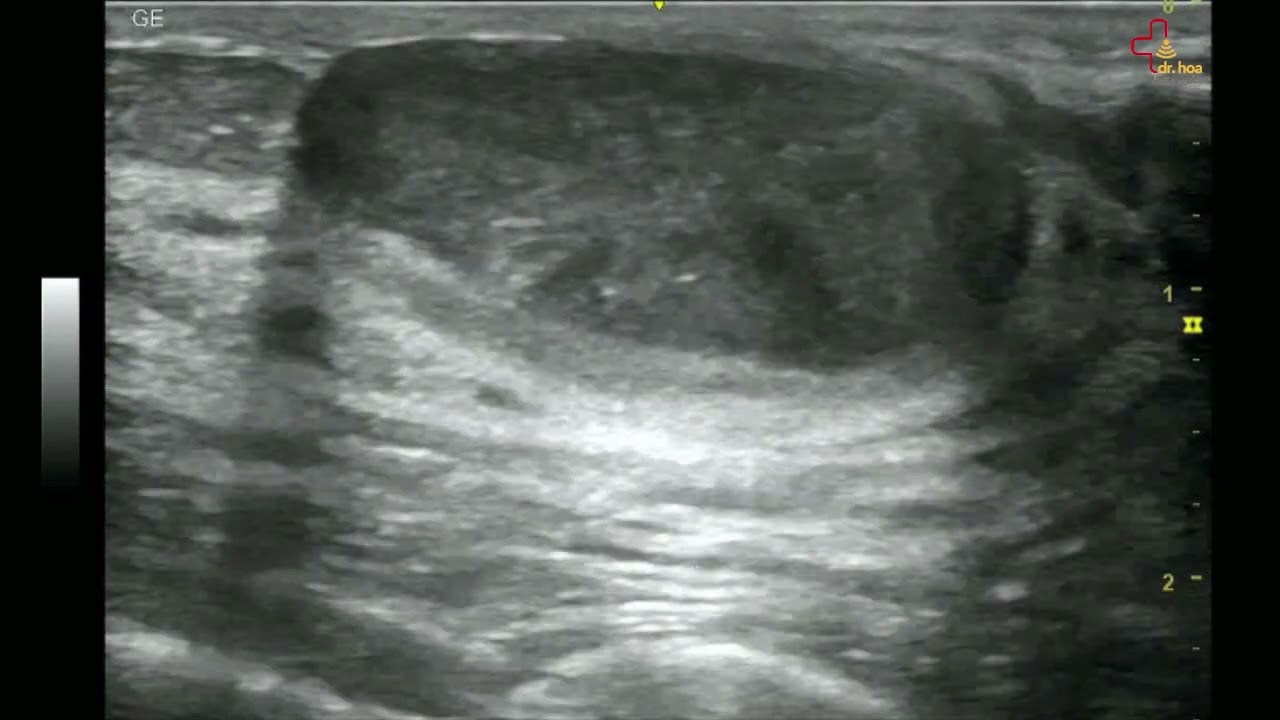

Sieu am Q7 xin gioi thieu case sieu am tuyen vu Buou soi tuyen dien hinh thuong gap o phu nu tre

Siêu âm Q7 xin giới thiệu case #siêu_âm_tuyến_vú : Bướu sợi tuyến điển hình thường gặp ở phụ nữ trẻ!